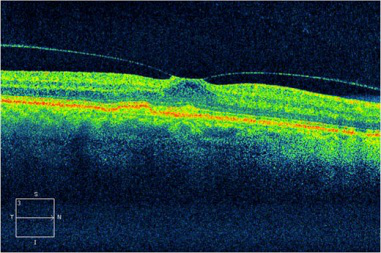

當葡萄膜炎影響到黃斑區域或視神經時,則可能會出現黃斑前膜、黃斑及視神經水腫、視神經炎、視網膜下新生血管等容易對視力容易致盲的并發癥。

(OCT檢查顯示眼睛的黃斑前膜,纖維膜在黃斑表面產生牽拉的力量,可引致黃斑水腫或裂孔,引致視野中央出現暗點)